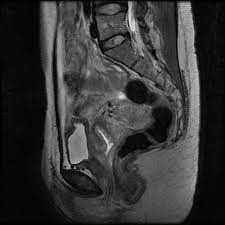

Magnetic resonance imaging or mri of the female pelvis offers a unique display of the pelvic anatomy, including a woman's ovaries, uterus, and fallopian tubes. Start studying normal female pelvis anatomy. With its help, it is realistic to study the female pelvis and get comprehensive information about the state of all organs of the human body.

Congenital malformation of the uterus: The integrity, biomechanical properties and anatomical features of the female pelvis are important for carrying out the labor. It bisects the true conjugate and is slightly shorter than the anatomical transverse diameter. The pelvis, so called from its resemblance to a basin, is a bony ring, interposed between the movable vertebræ of the vertebral column which it supports, and the lower limbs upon which it rests;